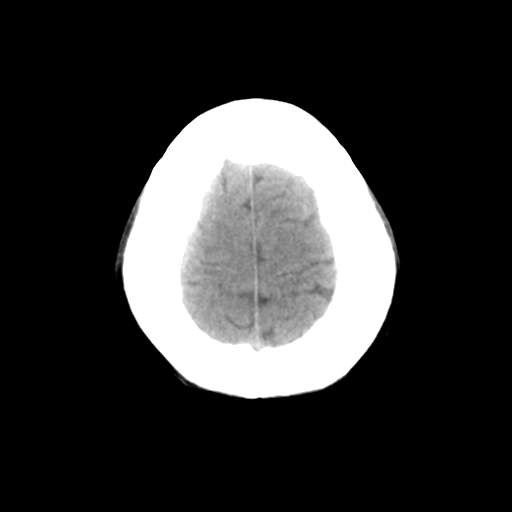

一台GE CT机突然出现下图伪影,请问是何原因?

并不是一直都有此伪影

这是设备原因造成的伪影一种伪影,

需要重新校准,

若不能矫正的话,那就没什么好办法了,

除非换配件

是不是原配球管啊,我院有台机器外圈有伪影是球管原因.

这种伪影一般还有个特点

在做薄层扫面时容易出现,一般是小于5mm,

但是在做常规10mm扫面时不会出现

这种现象并非一直出现,不分时间段,球管是租赁的,可能与电源有关

你有做一套的模和空气校正吗?没做好也会出这种情况的,一样是会有时好时坏的故障出的。